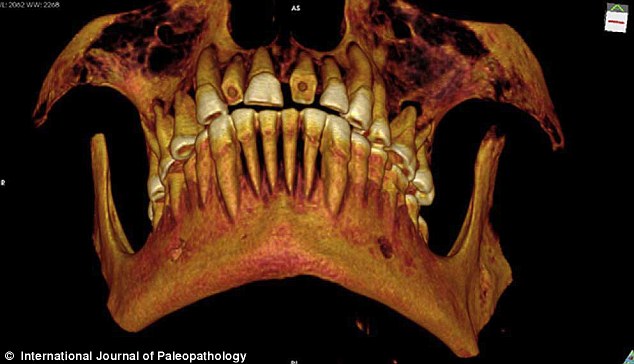

研究人员通过CT扫描图片观察木乃伊的口腔,并重建了一张显示磨损门牙的3D图。

《古病理学国际期刊》的文章称,来自加拿大西安大略大学的安德鲁·韦德利用一种新型高分辨率CT仪扫描木乃伊的牙齿和身体,并且根据扫描片重建了3D图以进行更为细致的研究。从CT扫描片可以看到,木乃伊的一颗牙齿龋洞里塞着一块亚麻布团。这块亚麻布之前可能经过无花果汁液或雪松油等药物的浸泡,随后被塞入下颚第一、二颗臼齿中间,也就是最大、也是最疼的龋洞里。这么做既能起到抵挡食物残渣进入龋洞的屏障作用,又能利用亚麻布上的药物缓解疼痛。